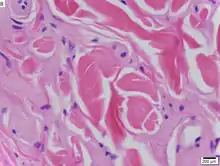

Urbach–Wiethe disease in skin biopsy with H&E stain.

The dermatological symptoms are caused by a buildup of a hyaline material in the dermis and the thickening of the basement membranes in the skin.[9] The nature of this material is unknown, but researchers have suggested that it may be a glycoprotein, a glycolipid, an acid mucopolysaccharide, altered collagen or elastic tissue.[6]